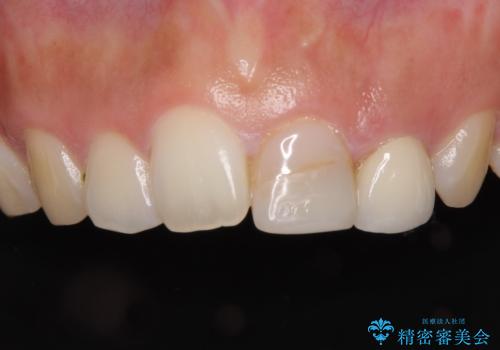

折れてしまって変色した前歯をオールセラミックに

- 中学生の時にスポーツで折ってしまった前歯が変色してしまったとのことで来院された患者様です。

結婚式に向けてオールセラミッククラウンにて仕上げていくこととしました。

既にクラウンが装着されていた歯は歯根の先端に病変が認められたため、根管治療を行うこととしました。